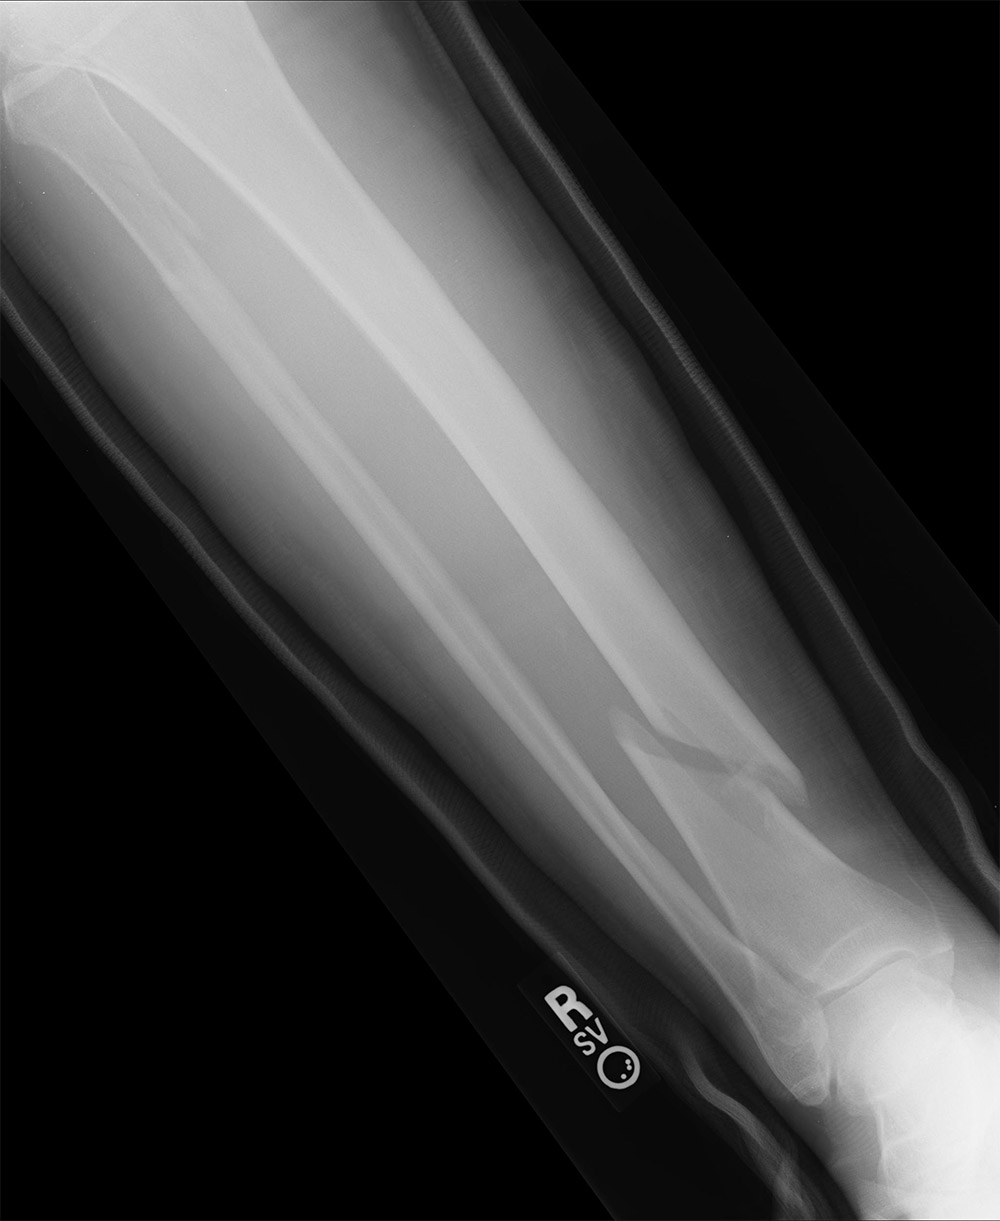

La fractura de tibia es una de las fracturas óseas más frecuentes y suele producirse por impactos de alta energía como accidentes de tráfico, atropellos o lesiones deportivas. Este tipo de fractura suele venir acompañada de otros problemas como lesiones en los ligamentos y, aunque el pronóstico en la mayoría de casos es bueno, el tiempo para una total recuperación podría hacer que Kade se pierda la primera ronda de la Copa del Mundo.